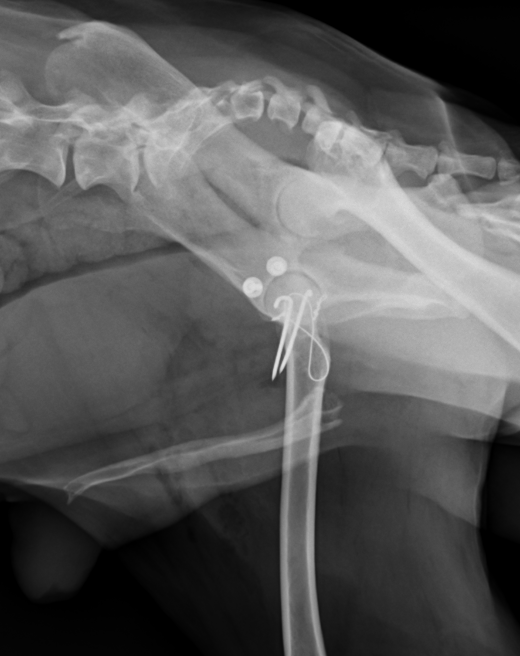

まずはワッシャーによる固定をご紹介します。大腿骨の大転子という部分を一時的に切断してから、骨盤臼にアプローチしてワッシャーを1つか2つ打ち込み、そこと大腿骨頭の骨頚部と呼ばれる部分に穴を開けてワイヤーを通し骨盤と大腿骨を固定する方法です。2週間ほど脱臼せずに維持できればその後は安定化していきます。

尾腹側脱臼では上記のワッシャーの方法は使用できず、トグルピン法か創外固定法、大腿骨頭切除の方法を用います。トグルピン方は、骨盤臼に穴を開け、そこにトグルピンと呼ばれる特殊な形のピンを挿入し、そこに引っ掛けた人工靭帯を、大腿骨に貫通させた穴に通して固定する方法です。この方法も2週間ほど維持できれば安定化していきます。